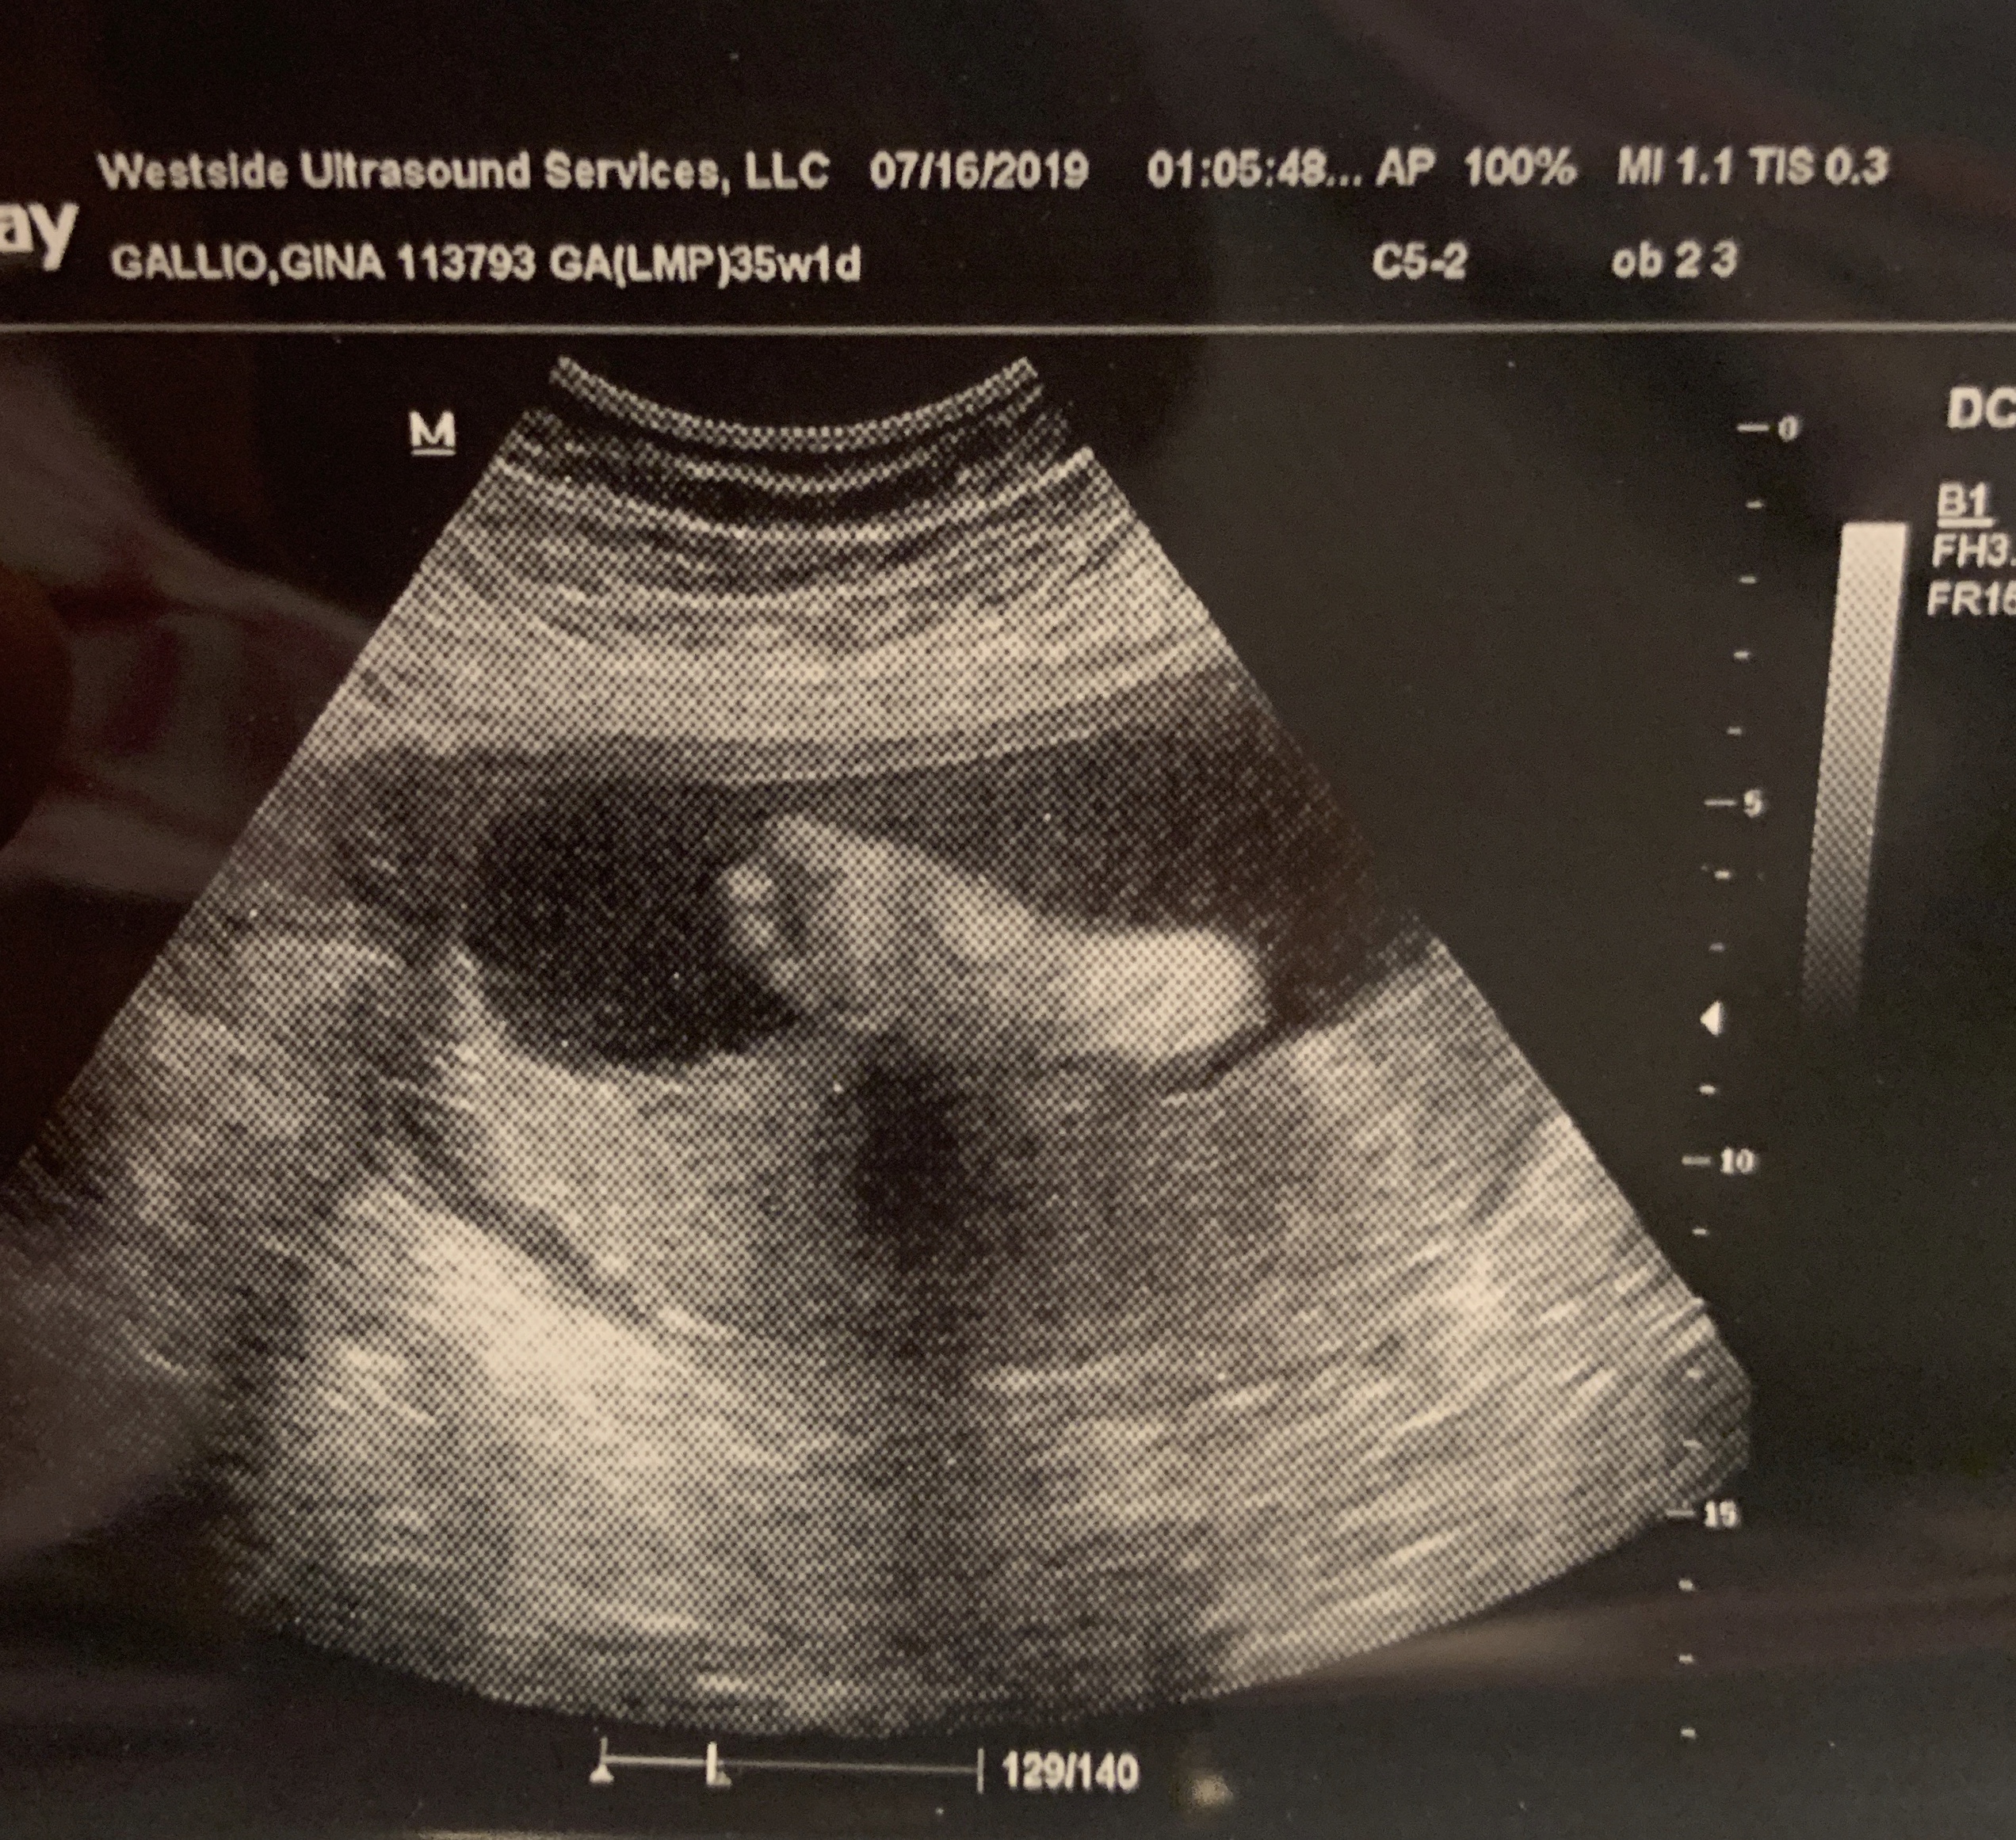

To My New Granddaughter » Bethany’s Foot